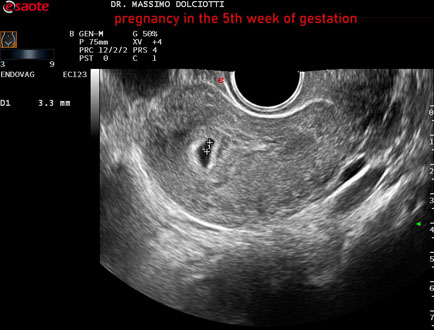

Strumento: Esaote MyLab Eight

Sonda: Convex Multifrequenza 1-8 MHz ed Endocavitaria Multifrequenza 3-9 MHz

Età Paziente: F 28 anni

Motivazione dell'esame: amenorrea e BETAHCG POSITIVO 17 mila.

Commento all'esame: le immagini ed il video documentano la camera gestazionale delle dimensioni di 13 x 7 mm e presenza di sacco vitellino delle dimensioni di 3,3 mm.

Conclusioni: gravidanza alla quinta settimana di gestazione (pregnancy in the 5th week of gestation).

Presentazione: Dr. Massimo Dolciotti - Ancona